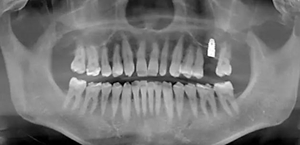

術(shù)前口內(nèi)照

術(shù)前CBCT檢查

骨高度不足,內(nèi)提升的適應(yīng)癥??梢姼]膜致密,厚度均勻。骨高度不足,骨寬度尚可。